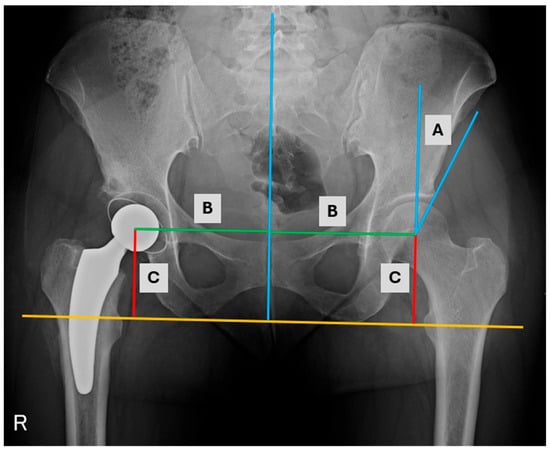

- Kołodziejczyk, K.; Czwojdziński, A.; Sionek, A.; Czubak, J. Assessment of the endoprosthesis offset in a dysplastic coxarthrosis. Acta Orthop. Belg. 2022, 88, 541–548. [Google Scholar] [CrossRef] [PubMed]

| Medialization before THA (mm) | 111 (102–120) | 113 (104–119) | 0.9 * |

| Distalization before THA (mm) | 82 (75–87) | 79.5 (72–83) | 0.17 * |

| Medialization THA (mm) | 91 (88–95) | 92.5 (87–99) | 0.53 ** |

| Distalization THA (mm) | 79 (73–83) | 74.5 (69–77) | 0.004 ** |